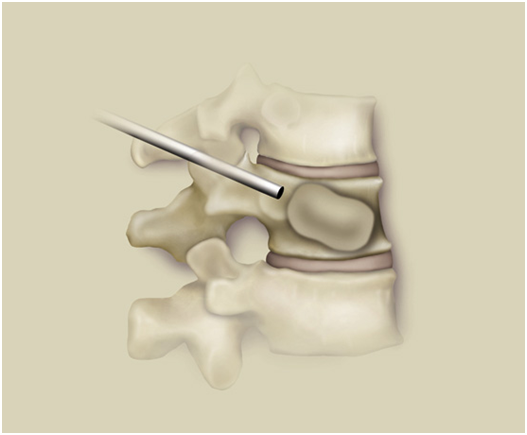

基本原理

通过工作通道置入球囊。

在体外通过压力泵给球囊加压。

负压取出球囊。

向空腔中注入骨水泥。椎体高度恢复,强度恢复。

使用球囊扩张可更安全、更有效,主要有以下两点优势:

避免井喷效应:球囊扩张产生空腔,骨水泥主体被注入空腔中,大大减少了渗漏。

矫正后凸畸形:球囊扩张能支撑起塌陷的椎体,部分地恢复椎体的高度,矫正后凸畸形。